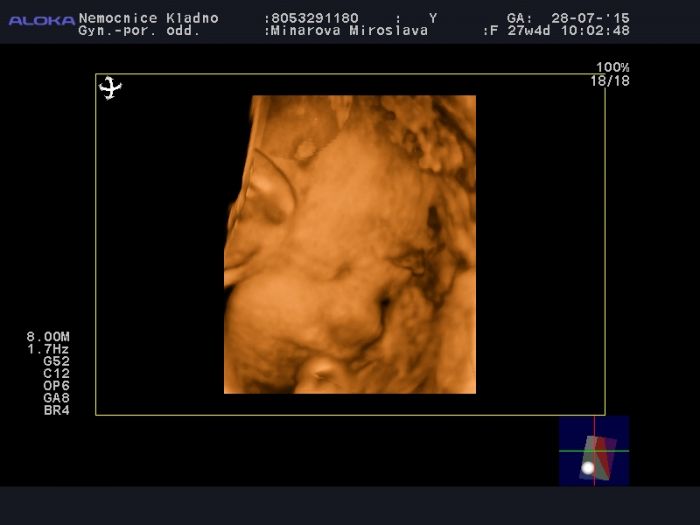

Ahoj, tak jsme po KO a UTZ. Ledviny jsou vpořídku 6 a 6 mm

Přikládám fota a mini video, ale nevím, jestli se ukáže nebo půjde pustit

Mimčo se pořád schovávalo za ručičky, všude lítaly nožičky a cucalo si pupečník

Nejdřív jsem běhala a poskakovala po místnosti a když to nepomohlo, poslali nás na cukrovou bombu, aby to mimčo uspalo. Tak jsem do sebe hodila čoko z automatu se sušenkou

Sice začalo víc kopat, ale natočilo se a opravdu po 10ti minutách usnulo, tak jsme rádi, že jsme z toho dostali aspoň tohle.